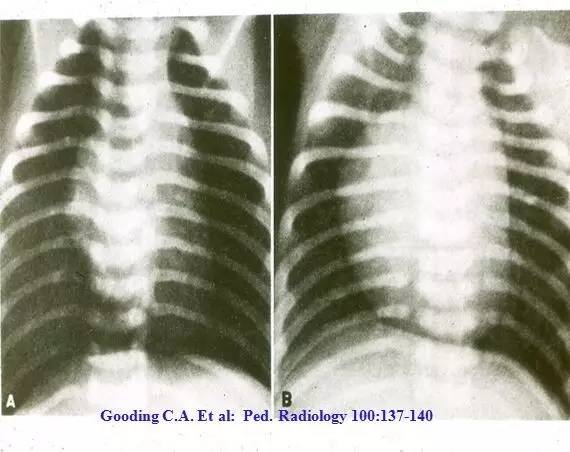

MAS影像学表现

临床和研究结果临床特征肺功能影像学图片